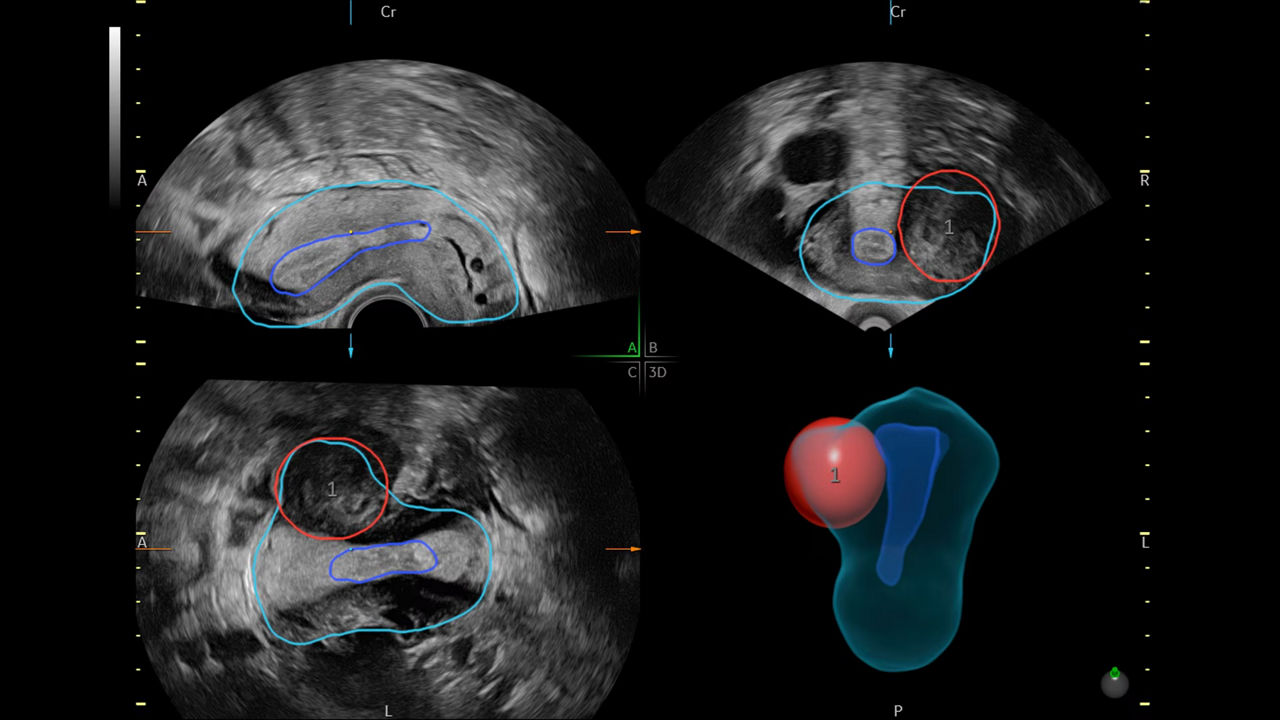

Identify fibroids 88% of the time with Fibroid Mapping